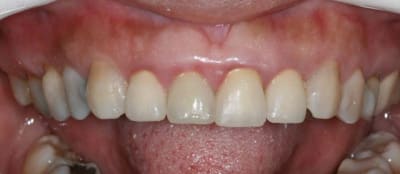

entre temps il y a de l'odf pr réaligner les incisives du bas(diastèmes se modifient d'après la patiente), à la demande de la patiente et parceque la fracture de 11 au bout de tant d'années me questionne...

la CCM est en prov de luxe

(ça tombait bien,la teinte est moyenne,bien qu'elle passe mieux en bouche que sur la photo:le flash?)

la patiente part en vacances

je la referai en septembre

avec ou sans chir?...

il y a eu remodelage naturel(comme quoi entre la theorie et la clinique): peut on le considérer comme suffisant?